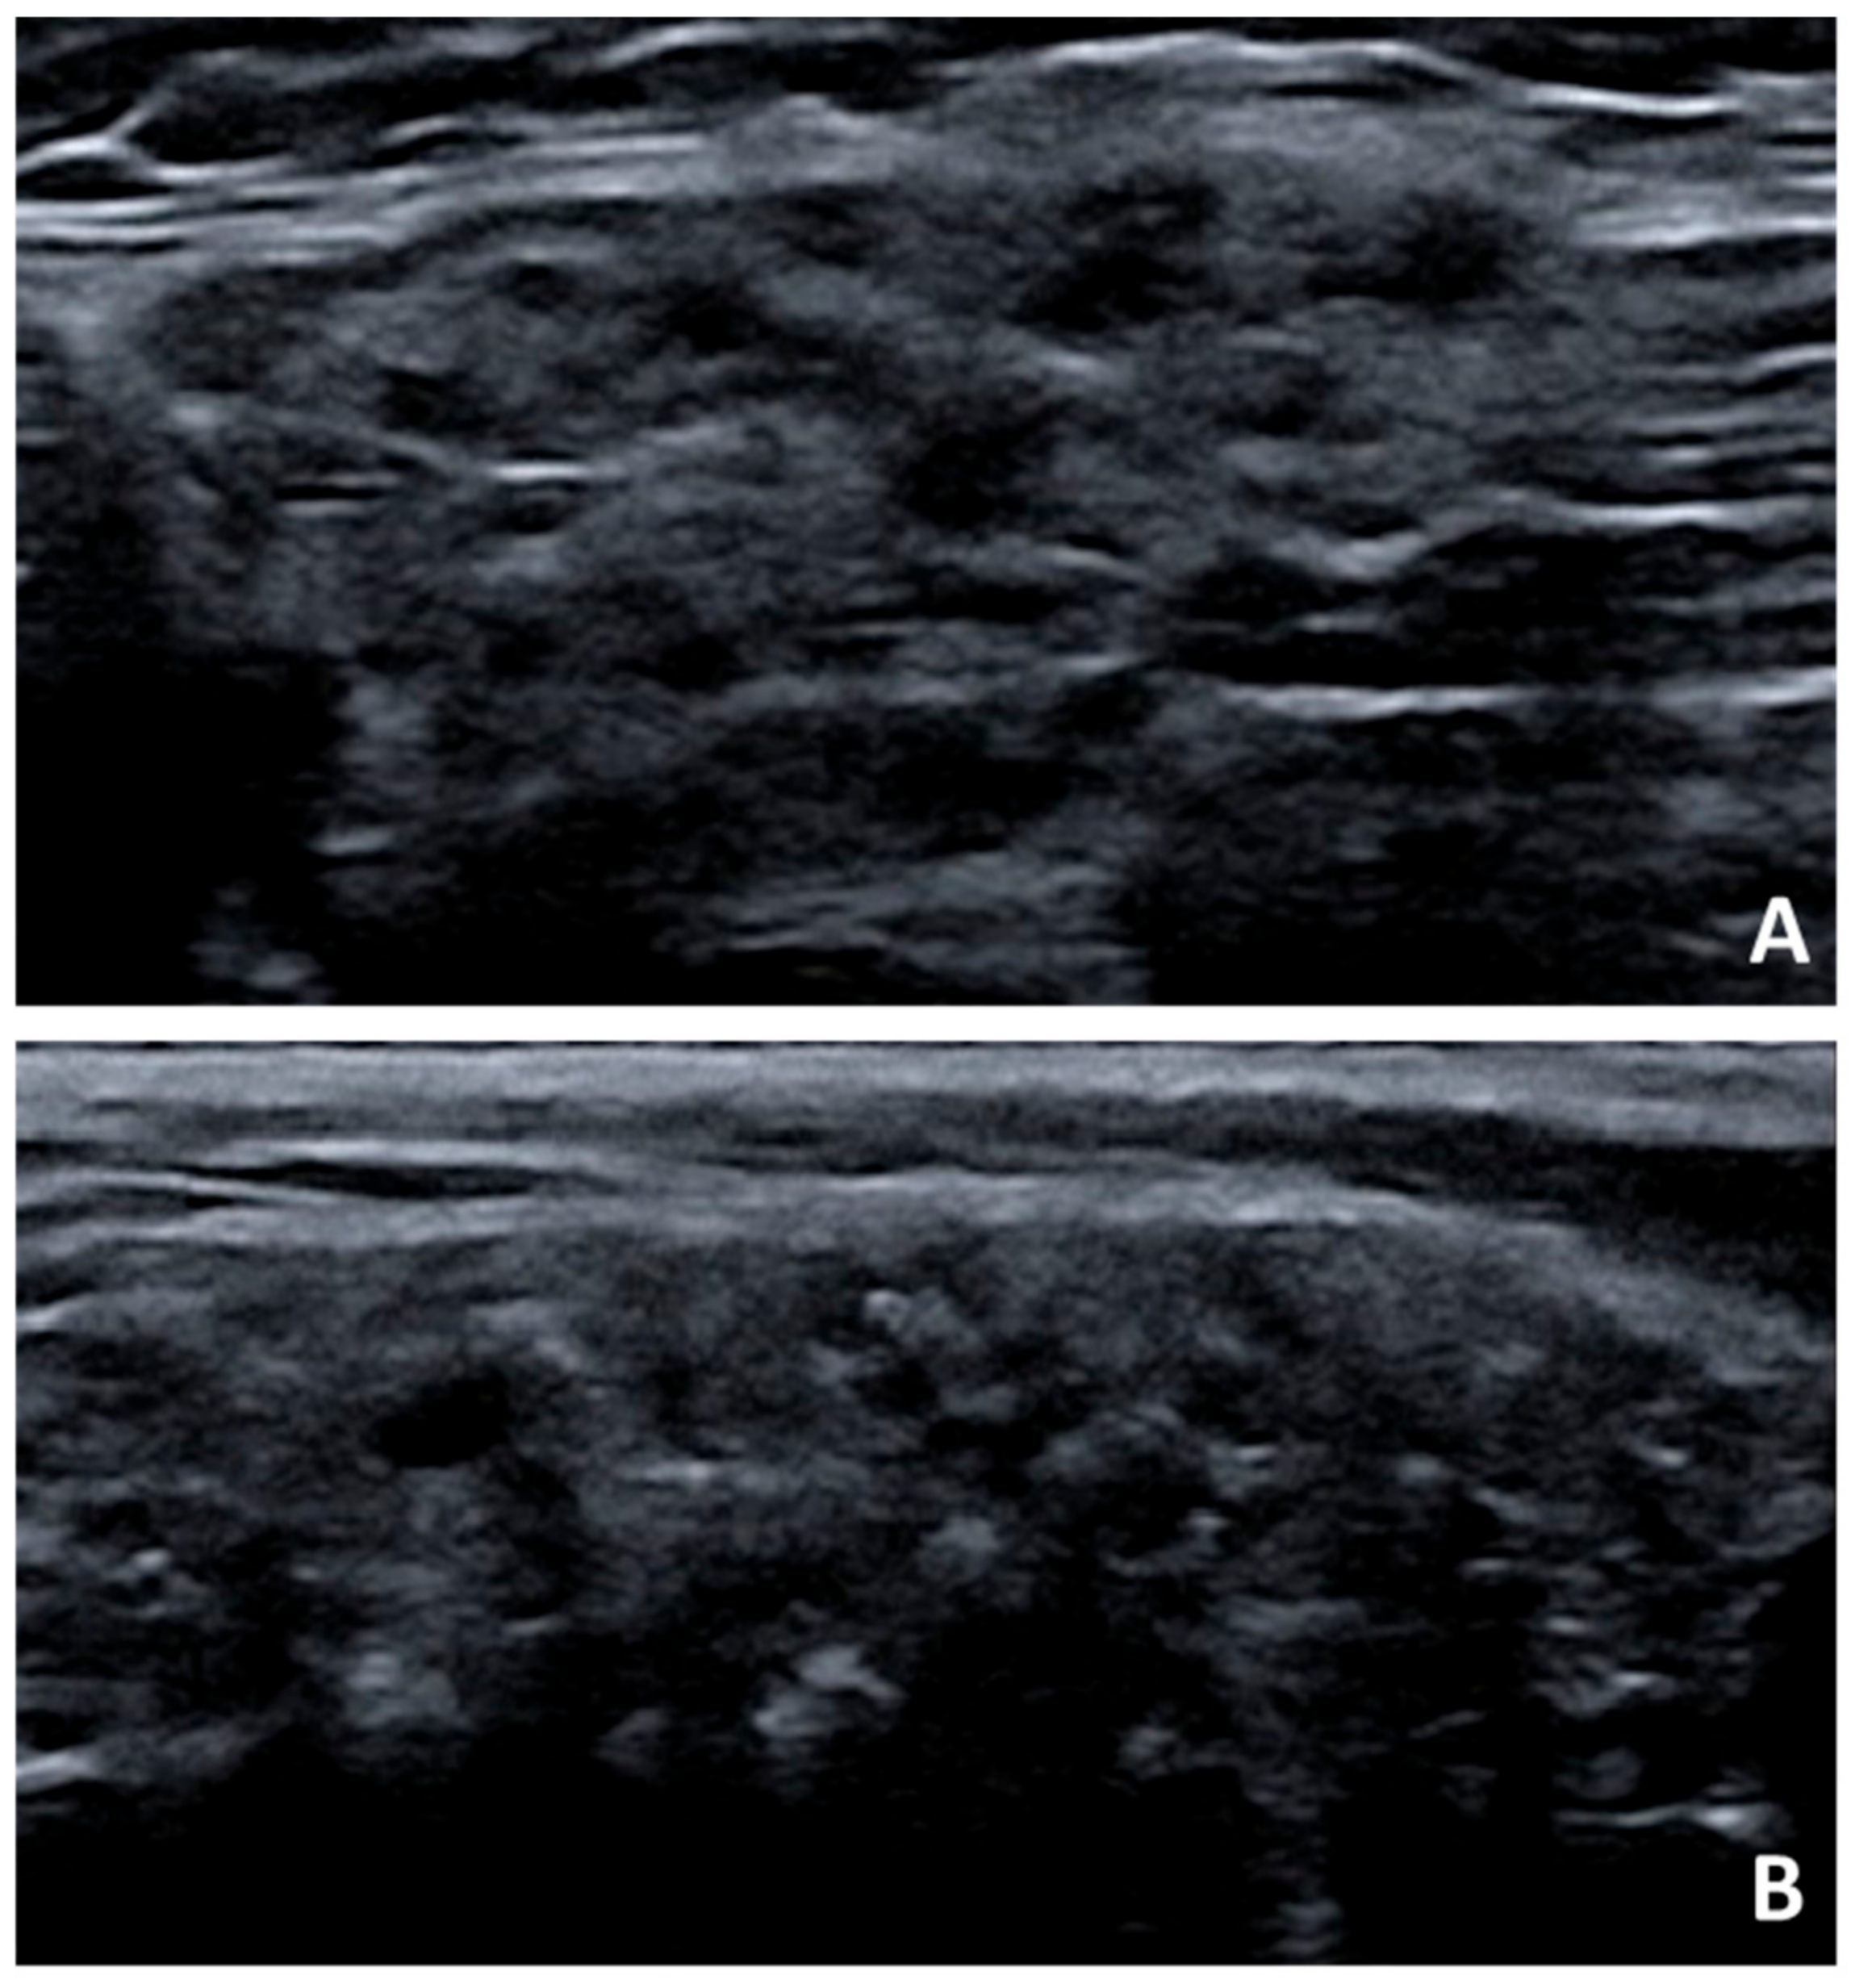

- Mossel, E.; Arends, S.; Van Nimwegen, J.F.; Delli, K.; Stel, A.J.; Kroese, F.G.M.; Spijkervet, F.K.L.; Vissink, A.; Bootsma, H. Scoring hypoechogenic areas in one parotid and one submandibular gland increases feasibility of ultrasound in primary Sjögren’s syndrome. Ann. Rheum. Dis. 2018, 77, 556–562. [Google Scholar] [CrossRef] [PubMed]

- Mossel, E. Comparing ultrasound, histopathology and saliva production of the parotid gland in patients with primary Sjögren’s syndrome. Unpublished work.

- Zabotti, A.; Callegher, S.Z.; Gandolfo, S.; Valent, F.; Giovannini, I.; Cavallaro, E.; Lorenzon, M.; De Vita, S. Hyperechoic bands detected by salivary gland ultrasonography are related to salivary impairment in established Sjögren’s syndrome. Clin. Exp. Rheumatol. 2019, 37, S146–S152. [Google Scholar]

- Theander, E.; Mandl, T. Primary Sjögren’s syndrome: Diagnostic and prognostic value of salivary gland ultrasonography using a simplified scoring system. Arthritis Care Res. 2014, 66, 1102–1107. [Google Scholar] [CrossRef]